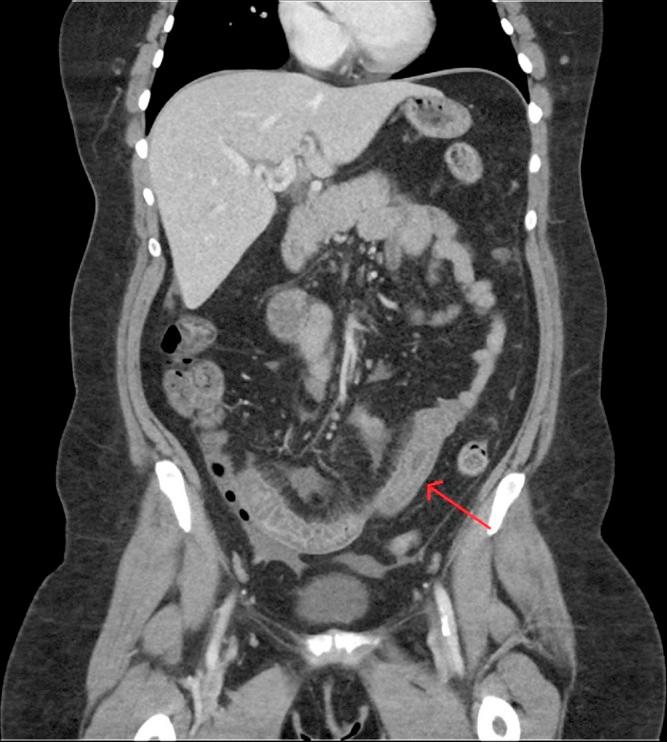

Intestinal angioedema is a rare side effect of angiotensin-converting enzyme inhibitors. We present a 41-year-old woman with sporadic right lower quadrant abdominal pain and diarrhea with multiple computed tomography scans demonstrating enteritis. Suspicion turned to angiotensin-converting enzyme inhibitor use as the cause for the patient's illness after an extensive negative evaluation including labs, stool studies, endoscopies, and capsule endoscopy. Weeks after stopping the medication, the patient's symptoms improved and repeat computed tomography showed a resolution of the previously seen findings of enteritis. This case illustrates the importance of a good medication review to make appropriate clinical decisions and diagnoses.

肠道血管性水肿是血管紧张素转换酶抑制剂的一种罕见副作用。我们报告一名41岁女性,有散发性右下腹腹痛和腹泻,多次计算机断层扫描显示为肠炎。在进行包括实验室检查、粪便研究、内镜检查和胶囊内镜检查在内的广泛阴性评估后,怀疑病因是血管紧张素转换酶抑制剂的使用。停药数周后,患者症状改善,重复计算机断层扫描显示先前所见的肠炎表现已消退。该病例说明了进行良好的用药回顾以做出适当临床决策和诊断的重要性。